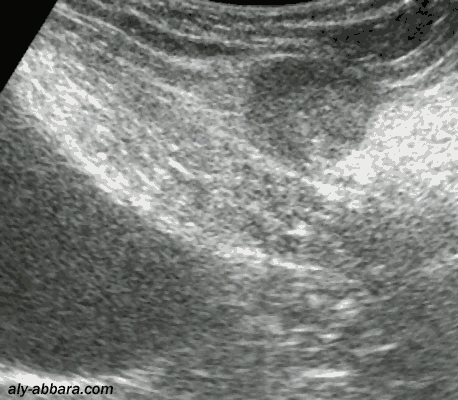

Noyau (de 25 x 20 mm) endométriosique localisé dans la paroi abdominale (sous-aponévrotique)

Il s'agit d'une localisation pariétale survenant suite à une césarienne réalisée deux ans auparavant

Il est à l'origine d'une douleur bien localisée, répétitive et cyclique, lors de chaque règles.